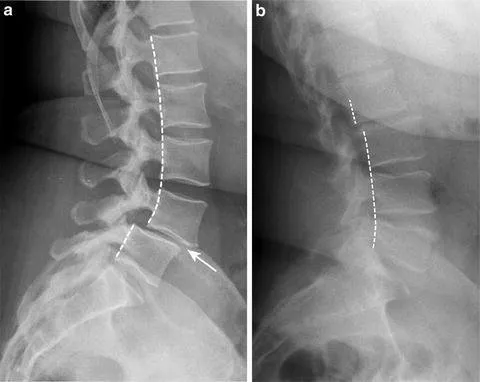

Radiografiile dinamice (flexie–extensie) diferențiază între un spondilolistezis stabil – cu alunecare constantă –

și unul mobil, cu translație suplimentară în mișcare. Instabilitatea dinamică este un argument important

în favoarea stabilizării chirurgicale, atunci când simptomatologia este semnificativă.

- Radiografii lombare AP și profil – confirmă alunecarea, conturează gradul și eventuale anomalii de tranziție.

- Radiografii dinamice (flexie–extensie) – apreciază instabilitatea segmentară prin variația unghiului și a translației între corpuri vertebrale.